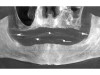

Fig 3. Implant planning for the mandibular arch for the patient of

Case Study 1.

Figure 3

Six implants were planned for both the maxillary and the mandibular arches, respectively (Figure 2 and Figure 3). A dual-arch CBCT was taken (Dentri-Max, HDX WILL; alternatively: CS 9600, Carestream; Explorer PRO, PreXion). The CBCT planning data was sent to the manufacturers to fabricate computer-